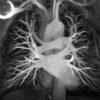

vessesls MR